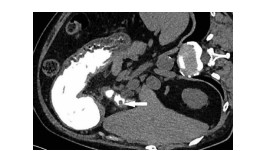

原发性肝淋巴瘤伴贫血和低蛋白血症1例报告

2021, 37(8): 1911-1913. DOI: 10.3969/j.issn.1001-5256.2021.08.034

摘要(963) HTML (226) PDF (2390KB)(53)

摘要: